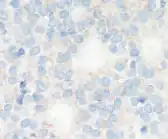

Micrographs showing each score:[46]

0

0 -

1+

1+ -

2+

2+ -

3+

3+